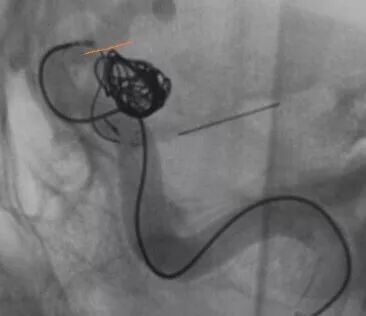

Enterprise4.5×22支架半释放,支架尾端的有效段能恰好覆盖全瘤颈

支架有效段完全释放,这个时候开始将支架导管往前顶,让导管头端尽量越过瘤颈远端

支架完全释放

释放后的造影。突入颈内动脉和后交通动脉内的弹簧圈被压入瘤体内

继续填塞,后面就简单了。最后的结果,一共用了四枚弹簧圈,栓塞致密,瘤体及破口都不显影了

顺利完成手术。几点体会:1、支架要选用Enterprise或LVIS jr,好定位。2、支架末端够用就行,不能留得太长。3、弹簧圈不要先解脱,支架释放成功再解脱,一旦失败还有余地。4、推导管的时候要拽着支架推送杆,不要让支架提前意外解脱了。5、颈内动脉瘤颈以远太细或有狭窄的不建议。6、缺点是技术稍显复杂,优点是能很好的将瘤颈填致密,难度不大,适合的病例可以选择。在此感谢各位长期指导我的教授及专家。感谢冯雷教授的经验分享。